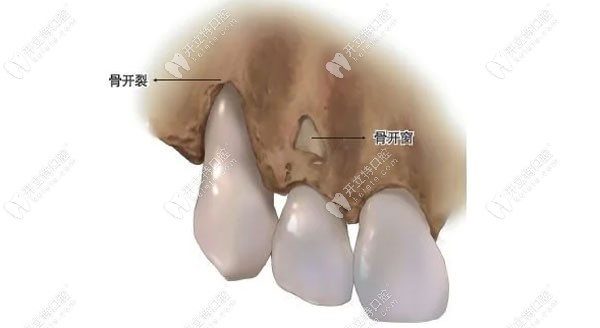

骨开裂和骨开窗图片

骨开窗示意图

正畸形成骨开窗和骨开裂有啥区别?看骨开窗示意图自行判断

骨开窗,骨开裂示意图

正畸形成骨开窗和骨开裂有啥区别?看骨开窗示意图自行判断